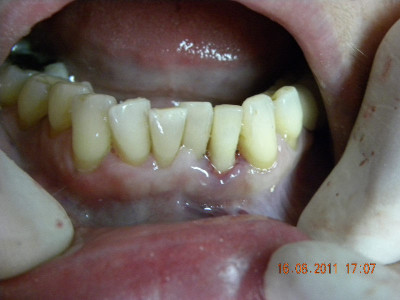

Colocación de implante y carillas libres de metal

Envíado por Grupo Dental de El Salvador